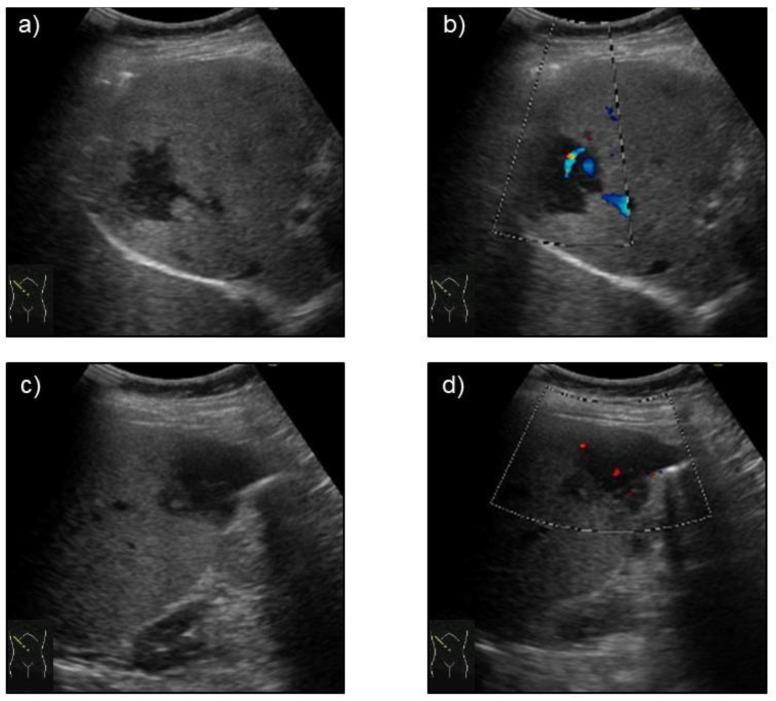

The incidence of extranodal marginal zone lymphoma of mucosa-associated lymphoid tissue (MALT lymphoma) is low, at 7-8% of all non-Hodgkin lymphoma cases. The most common site of MALT lymphoma occurrence is the stomach. Primary hepatic extranodal marginal zone lymphoma of MALT is classified as a type of non-gastric MALT lymphoma and is considered extremely rare, with no consensus on imaging study findings or treatment due to a limited number of reports. We herein describe a rare case of primary hepatic extranodal marginal zone lymphoma of MALT with underlying hepatitis B infection (HBV) and present useful diagnostic findings of various imaging modalities, including contrast-enhanced ultrasonography (CEUS) with Sonazoid.

A 66-year-old woman was diagnosed as being a non-active carrier of HBV at 51 years of age at the time of total hysterectomy and bilateral adnexectomy for uterine cervical cancer. She was admitted to our hospital following the incidental detection of two focal liver lesions on computed tomography. The lesions were considered malignant based on clinical and other radiologic imaging findings. Her CEUS results of hypo-enhancement in the portal and late phases were consistent with those of previously reported cases of hepatic extranodal marginal zone lymphoma of MALT, and histological liver biopsy findings were compatible with the diagnosis.

Primary hepatic extranodal marginal zone lymphoma of MALT is a rare condition that can appear in HBV carriers. Characteristic CEUS findings may help in disease diagnosis. Clinicians should bear primary hepatic extranodal marginal zone lymphoma of MALT in mind when encountering patients with focal liver lesions which exhibit image findings different from those of typical hepatocellular carcinoma.

黏膜相关淋巴组织结外边缘区淋巴瘤(MALT淋巴瘤)的发病率较低,占所有非霍奇金淋巴瘤病例的7-8%。MALT淋巴瘤最常见的发生部位是胃。原发性肝MALT结外边缘区淋巴瘤被归类为非胃MALT淋巴瘤的一种类型,被认为极为罕见,由于报告数量有限,对于其影像学研究结果或治疗尚无共识。我们在此描述一例合并乙型肝炎病毒(HBV)感染的原发性肝MALT结外边缘区淋巴瘤罕见病例,并展示包括使用声诺维的对比增强超声(CEUS)在内的各种影像学检查的有用诊断结果。

一名66岁女性在51岁时因子宫颈癌行全子宫切除术和双侧附件切除术,当时被诊断为HBV非活动性携带者。在计算机断层扫描偶然发现两个肝脏局灶性病变后,她入住我院。根据临床和其他放射影像学检查结果,这些病变被认为是恶性的。她的CEUS在门静脉期和延迟期呈低增强的结果与先前报道的肝MALT结外边缘区淋巴瘤病例一致,肝脏组织活检结果与诊断相符。

原发性肝MALT结外边缘区淋巴瘤是一种可出现在HBV携带者中的罕见疾病。CEUS的特征性表现可能有助于疾病诊断。临床医生在遇到肝脏局灶性病变且影像表现不同于典型肝细胞癌的患者时,应考虑到原发性肝MALT结外边缘区淋巴瘤。